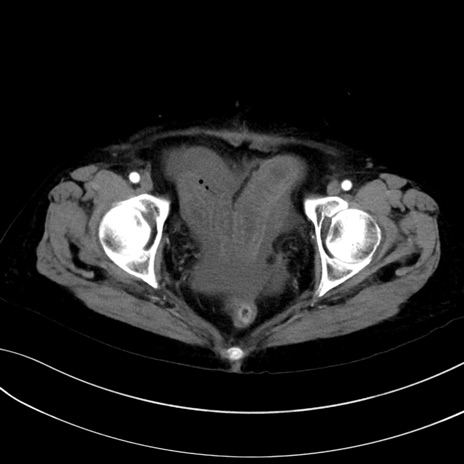

症例13 CT(横断像)1日半後